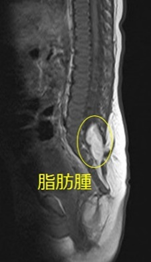

脊髄脂肪腫は、脊髄が形成される過程で脂肪組織が入り込んでくることが原因で生じます。皮下脂肪が脊髄までつながって脊髄を圧迫し、さらに脊髄が脂肪腫によって牽引され脊髄係留という状態になります。全く無症状のこともありますし、下肢の麻痺や排尿排便障害などの症状がすでに出ていることもあります。脂肪“腫”という病名ですが、“腫瘍”ではなくあくまでも脂肪の塊です。大きくなったり転移することはありません。

無症状の場合に手術を行うかは年齢や難易度によって個々に判断することになりますが、すでに症状がある場合には通常手術を行います。手術の目的は、無症状の場合は将来症状が出てくるのを防ぐことであり、すでに症状が出ている場合はこれ以上悪化するのを防ぐことです。

脂肪腫の付近には重要な神経が多数走行しています。当科の手術では、これらを1本も損傷しないように膀胱・直腸・下肢の神経モニタリングを併用して安全に脂肪腫の摘出を行なっています。